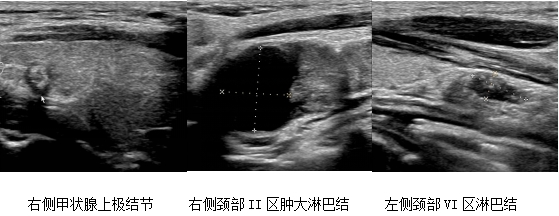

•案例一:青年患者小李发现颈部肿块,经超声检查提示甲状腺结节及淋巴结肿大。科室姬静伟医生行FNAB穿刺后,病理确诊为甲状腺乳头状癌合并淋巴结转移。安兆峰主任团队随即实施根治手术,清扫双侧颈部淋巴结71枚,其中20枚有癌转移。